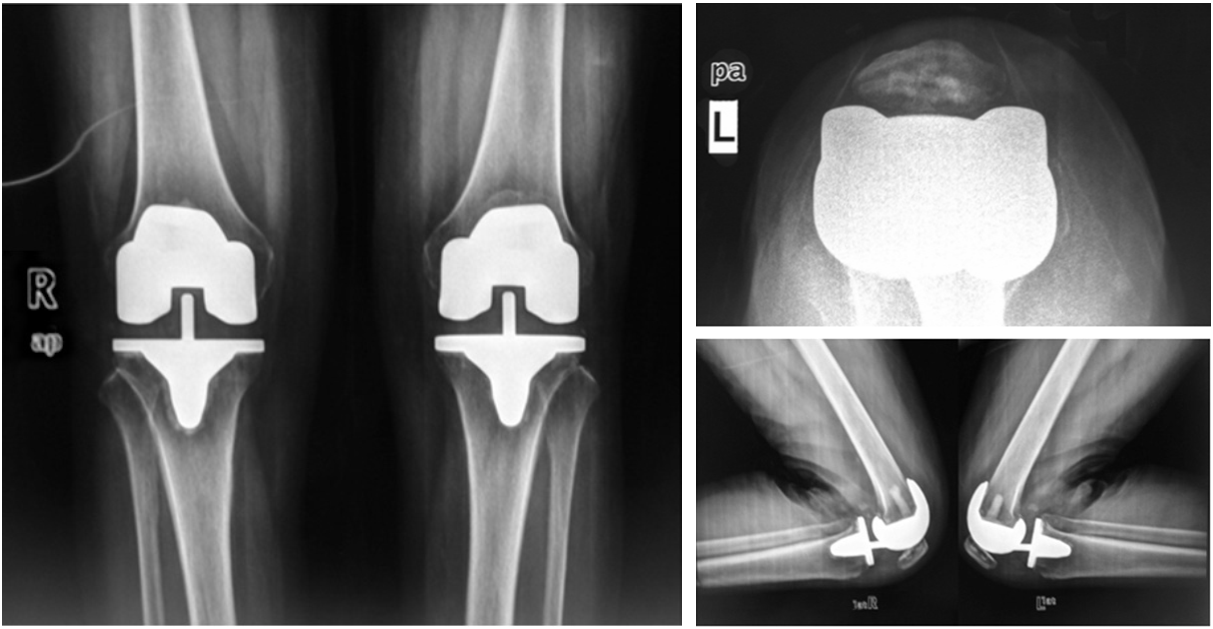

活动平台型假体置换术后X线片

注:L:左边;R:右边。

活动式负重面假体双髁接触面积大约是固定式负重面假体的5倍,接触应力可降至固定式负重面假体的1/5。在胫骨假体安装时,只需要考虑平台假体对胫骨面覆盖,安装后胫骨旋转可自动适应髌股滑动,避免因了胫骨旋转异常导致的髌股滑动轨迹异常,并可减少髌骨撞击综合征、髌股关节弹响和膝前痛。但滑动平台假体对侧副韧带稳定性及软组织平衡性要求更高,对于严重的膝内外翻畸形,术中需要广泛松解。侧副韧带相对脆弱的患者不宜使用旋转平台假体,因屈伸间隙不平衡及侧副韧带稳定性不良,可能出现旋转平台型假体聚乙烯衬垫脱出的情况。